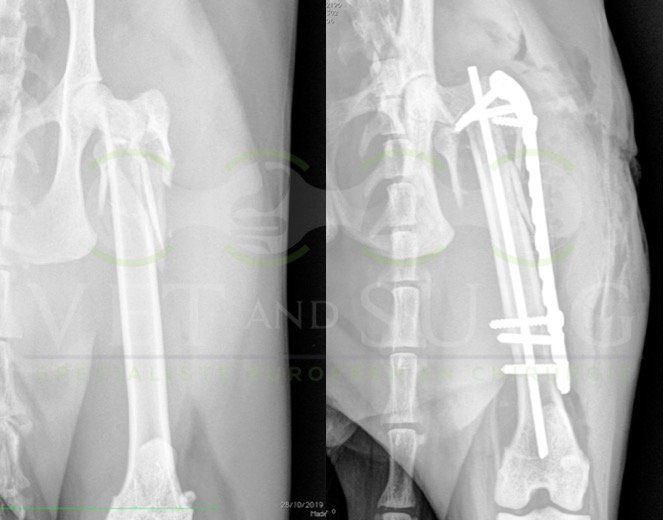

Fracture Salter-Harris sur un chaton Européen de 10 mois

Spike, chaton européen mâle de 10 mois, a été présenté en consultation pour boiterie du membre postérieur droit à la suite d'une chute depuis le 1er étage.

A la radiographie, une fracture de type Salter-harris 1 est diagnostiquée, avec déplacement de l'about discal.

Une réduction de la fracture par pose de 2 broches en croix a été réalisée.